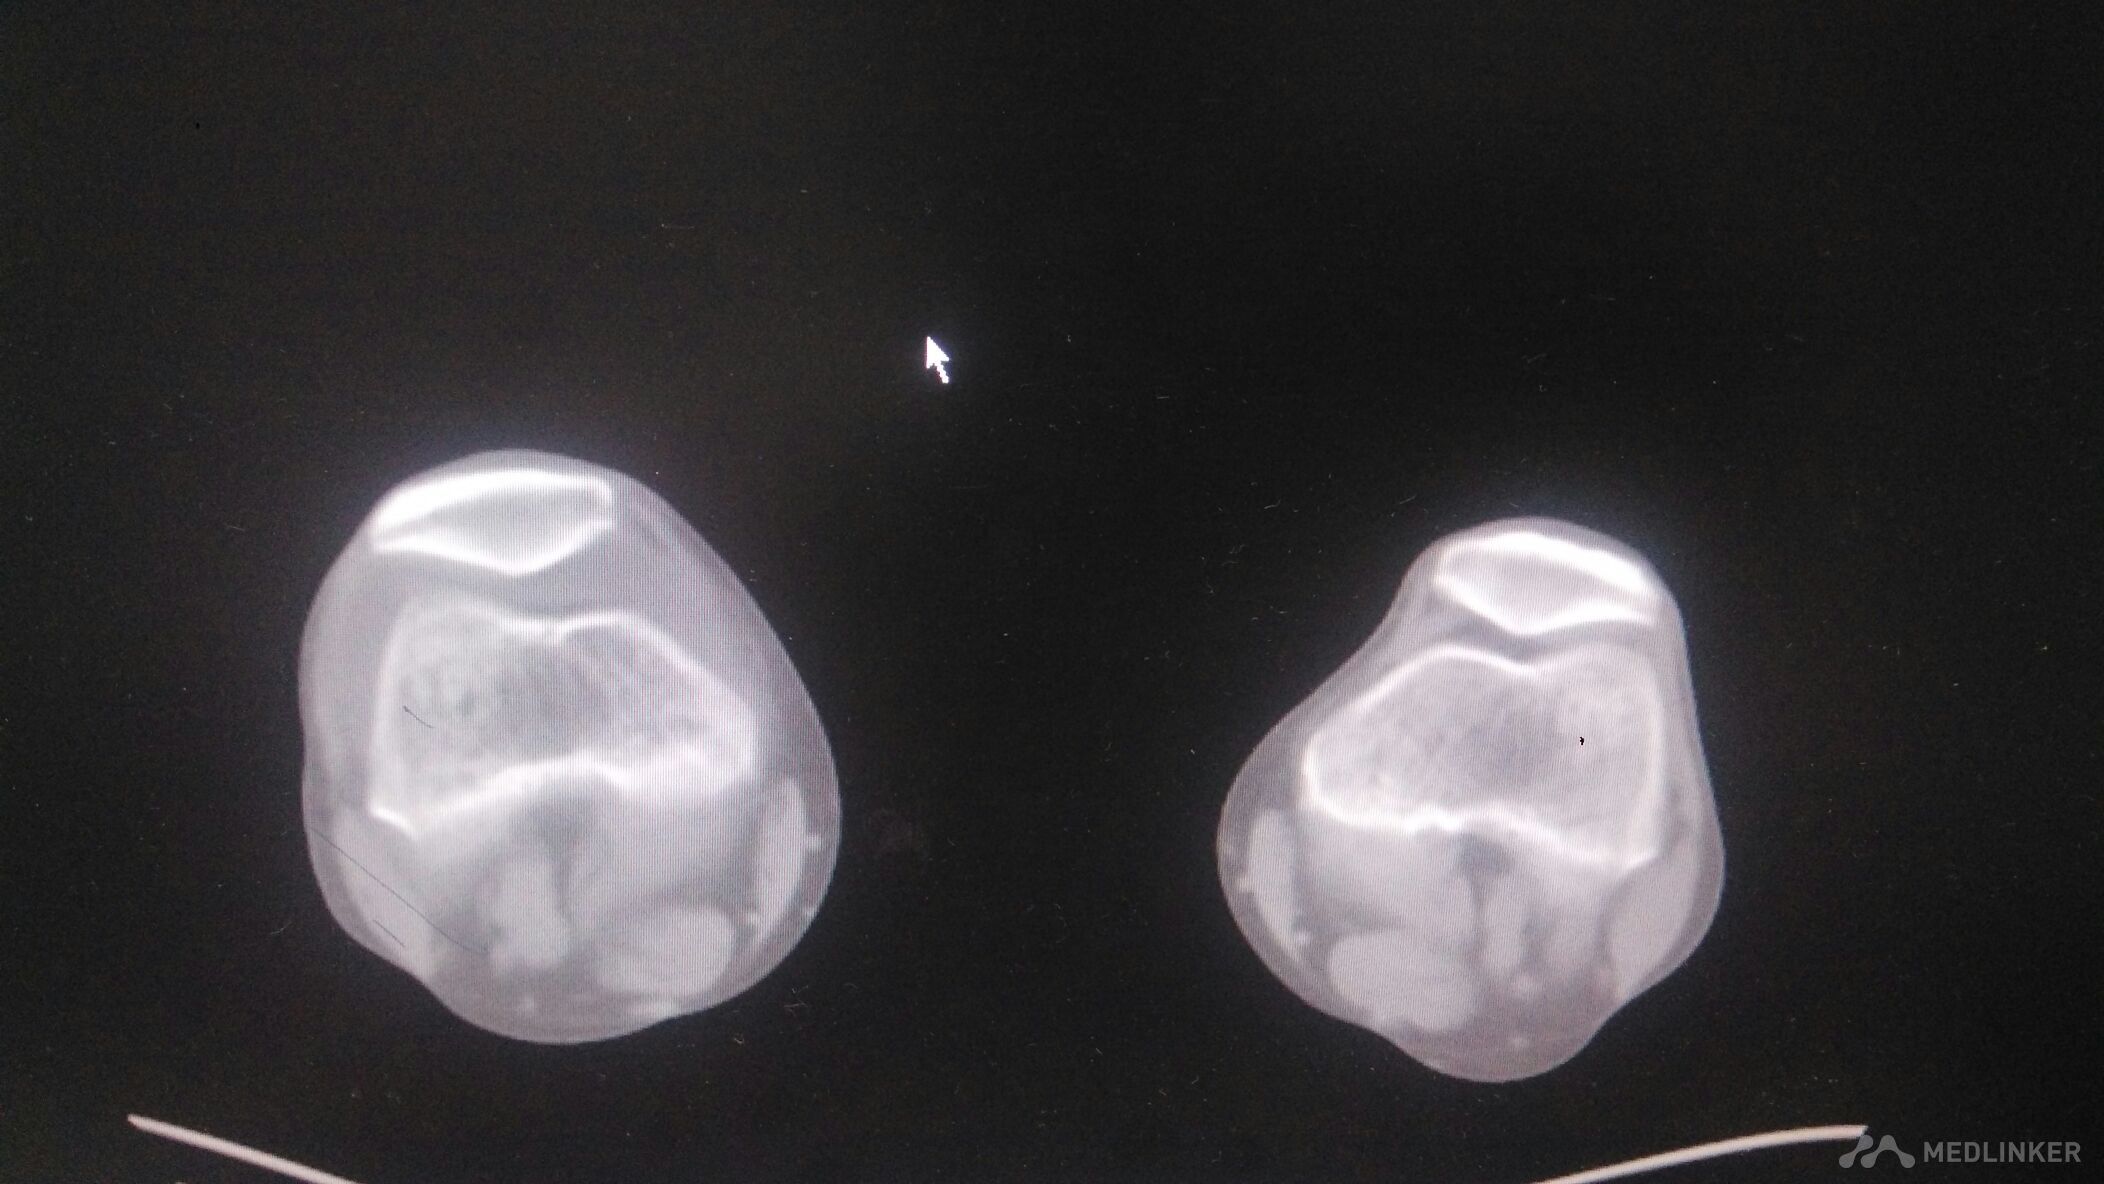

髌骨脱位

髌骨脱位的治疗?

青少年习惯性髌骨脱位手术治疗选择?

髌骨脱位有什么表现?